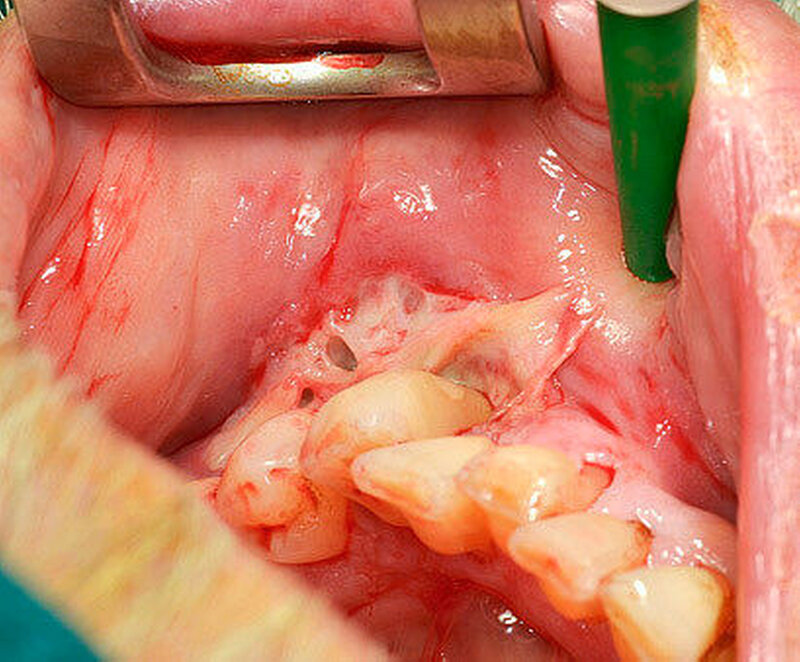

Der intraorale Befund zeigte neben einer moderat chronischen Parodontitis ein nekrotisierendes und ulzerierendes Schleimhautareal in regio 32 bis 35 (Abbildung 1). Überdies konnte eine Sondierungstiefe von 6 mm zwischen 32 und 33 sowie ein Lockerungsgrad von 1 bis 2 an den Zähnen 32 bis 34 bei positiver Sensibilität erhoben werden, wobei zumindest 2D-radiologisch kein Knochenabbau vorlag (Abbildung 2). Aufgrund des deutlich reduzierten Allgemeinzustandes des Patienten entschieden wir uns für eine stationäre Weiterbehandlung. Ein kurz darauf angefertigtes Blutbild zeigte unter anderem einen Hämoglobin-Wert von 5,2 mmol/l (Referenzbereich 8,6 bis 12 mmol/l), einen Hämatokrit-Wert von 0,24 (Referenzbereich 0,4 bis 0,51), einen Kernschatten-Wert von 40 Prozent (Referenzbereich 1 Prozent ) sowie einen CRP-Wert von 53,1 mg/l (Referenzbereich 5 mg/l).

Nach 48 Stunden i.v.-Antibiose und intensiver Hygienisierung (Abbildung 3) erfolgte die Abtragung der Gingivanekrose unter laufender Dabigatran-Medikation. Die sich von Zahn 32 bis 35 vestibulär und interdental erstreckende Nekrose wurde schonend entfernt (Abbildung 4). Eine Mitbeteiligung des Alveolarknochens war nicht erkennbar. Im Anschluss erfolgte eine chemische Dekontamination der Wunde mit Betaisodona-Lösung sowie der primäre Wundverschluss mittels modifiziertem koronalen Verschiebelappen (Nahtmaterial: Resolon 4.0, Resorba Medical GmbH). Die Zähne 32 bis 34 wurden aufgrund ihrer geringgradigen Lockerung belassen und mittels Säure-Ätz-Technik primär durch Schienung stabilisiert. Abschließend erfolgte die Abdeckung des OP-Situs mit einer Verbandsplatte, in welche im vestibulären Bereich eine Aussparung eingearbeitet wurde (Abbildung 5).